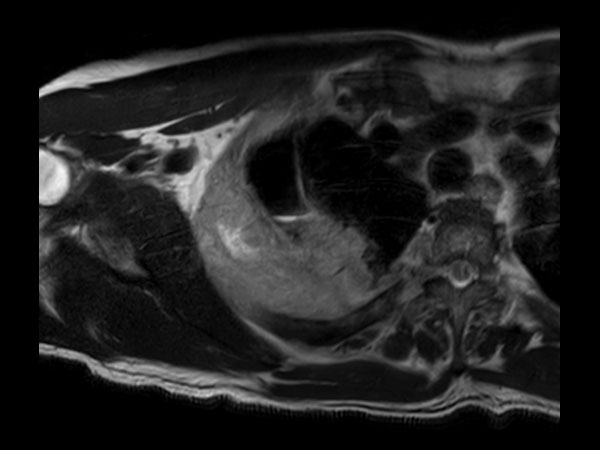

Axial T2w mDIXON XD TSE (In Phase)